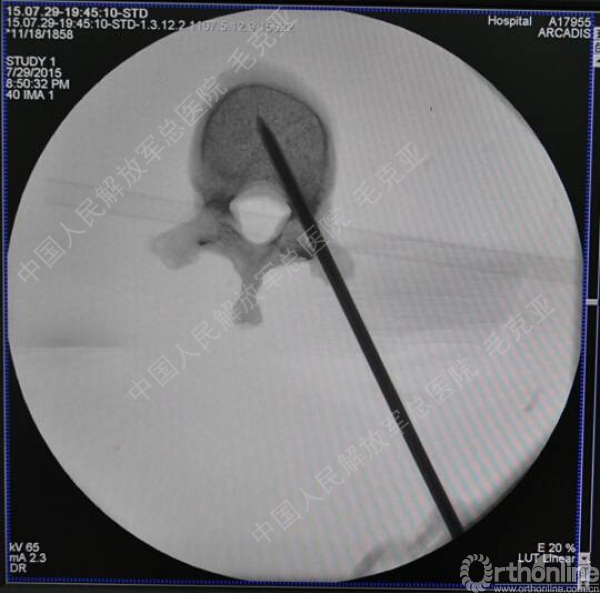

导语:随着社会老龄化的不断加速,骨质疏松性椎体压缩骨折作为一种普遍存在的老年骨科疾病已经成为现今骨科界的一个热点话题。传统的保守疗法治疗效果不佳,而现有的椎体增强技术又具有多种风险和缺陷。针对这种现状,中国人民解放军总医院毛克亚教授提供了一种新的解决方法。